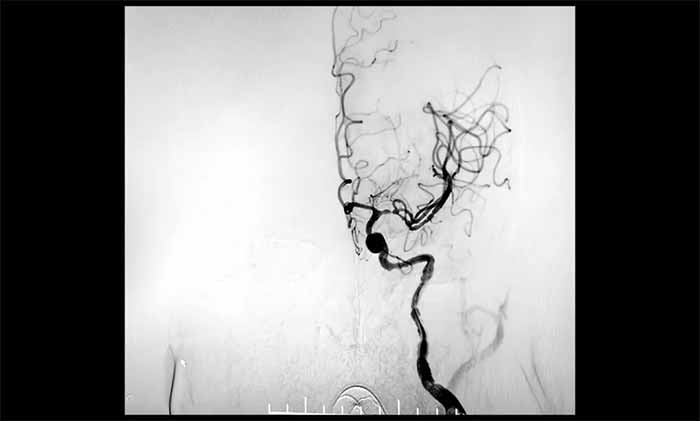

▲ 左頸內(nèi)動(dòng)脈順利開(kāi)通

二次取栓難度遠(yuǎn)超首次:患者處于恢復(fù)期,血管壁條件較差,存在出血轉(zhuǎn)化風(fēng)險(xiǎn)。在席剛明教授指導(dǎo)下,王貴平博士主刀的介入團(tuán)隊(duì)成功取出新鮮血栓,復(fù)查造影顯示血管再通,血流恢復(fù)良好。目前患者正在康復(fù)中。